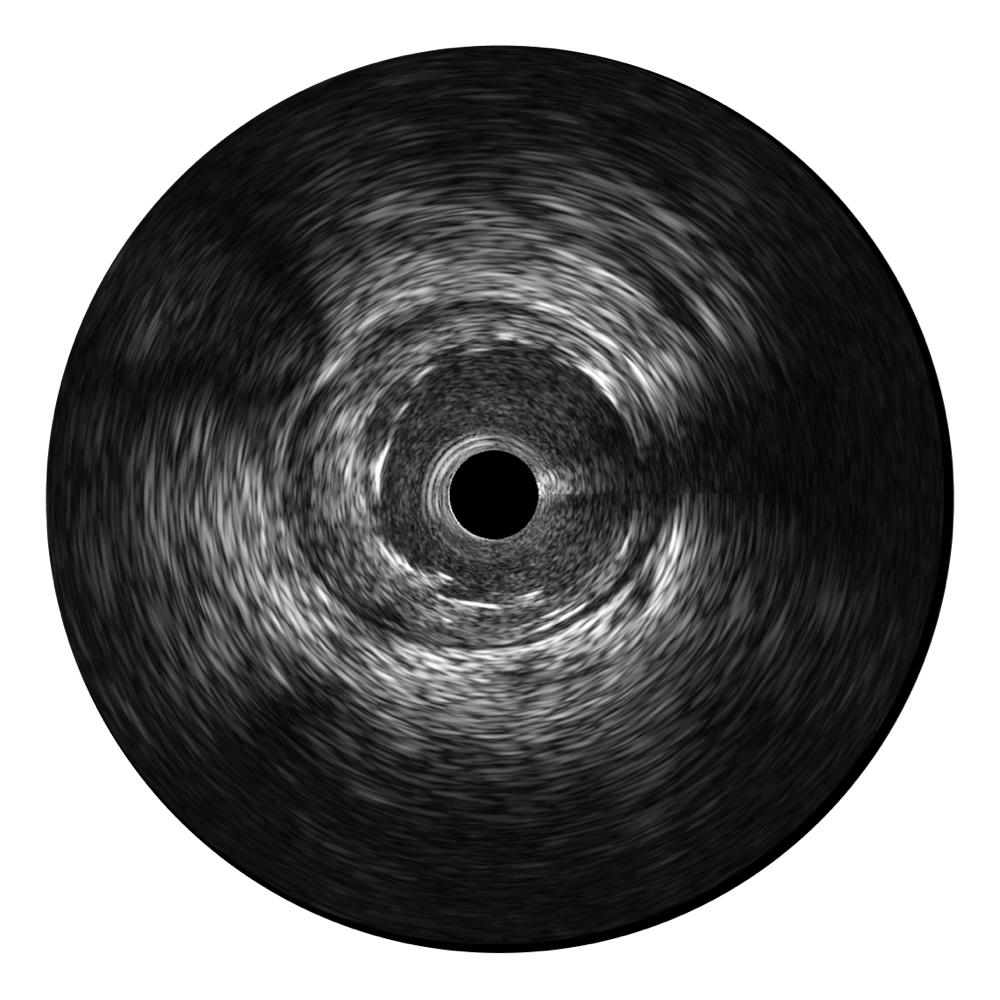

milan米兰宽频IVUS图像

对比传统IVUS导管成像,milan米兰宽频IVUS图像的近场支架梁显影更细腻,远场中膜外血管仍清晰可辨,兼顾远中近,兼顾分辨力与穿透深度